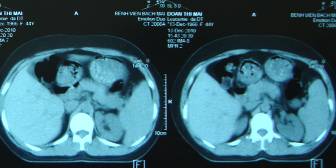

CT ổ bụng: gan-lách to, không có hạch ổ bụng, không có dịch ổ bụng